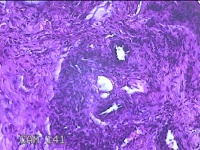

右侧肘后包块

性别

男

年龄

59岁

临床诊断

脂肪瘤

一般病史

发现右侧肘后包块1年余,无明显疼痛及不适。

标本名称

大体所见

灰白暗红色肿物1.3x0.5x0.3cm一个,表面糜烂。